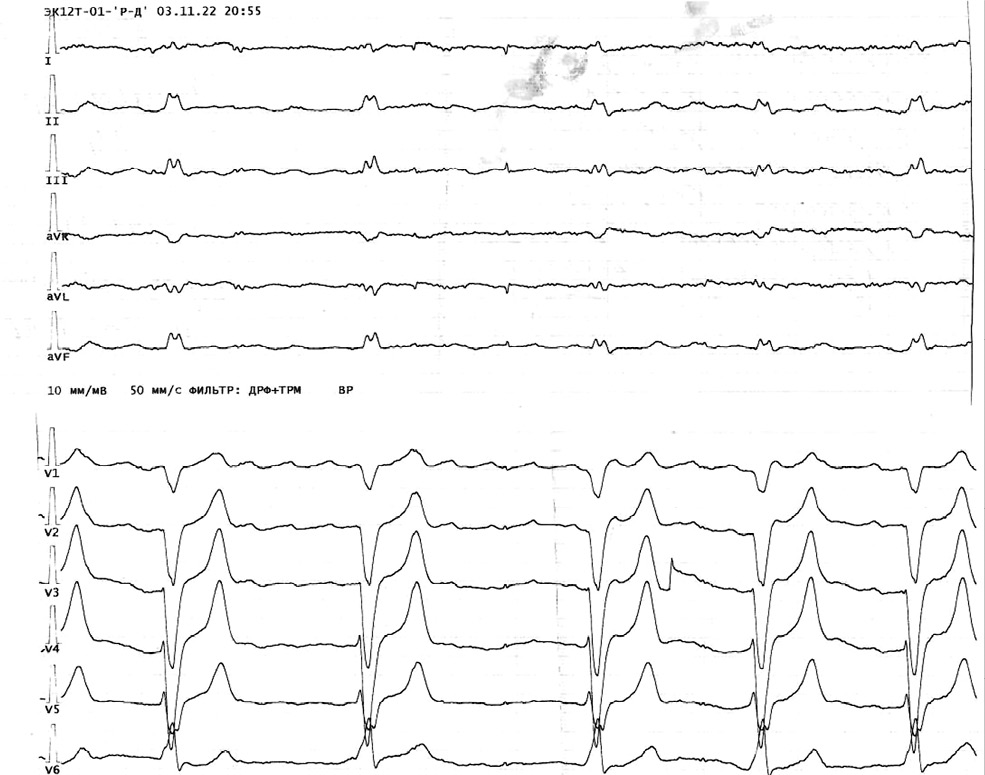

Из анамнеза известно, что 25.10.2022–31.10.2022 пациент проходил лечение в кардиологическом отделении этого же стационара с диагнозом: «Ишемическая болезнь сердца (ИБС): стенокардия напряжения. Постинфарктный кардиосклероз. Перманентная ФП, тахисиcтолическая форма. Хроническая сердечная недостаточность со сниженной фракцией выброса ЛЖ 29% IIА-стадии, III функционального класса. Хронический панкреатит». В связи с повышением температуры тела до субфебрильных цифр, расцененной как проявление острого респираторного заболевания, пациент был выписан из стационара досрочно, 31.10.2022. После выписки назначенную медикаментозную терапию (рамиприл, дигоксин, дапаглифлозин, аторвастатин, апиксабан) не принимал, отмечал повышение температуры тела до 40,0 °С. 01.11.2022 у пациента возникли жалобы на боль в животе, тошноту, рвоту, диарею (2–3 раза/сут). Участковым терапевтом была назначена терапия по поводу обострения хронического панкреатита. 03.11.2022 с 7:00 пациент отметил появление интенсивной боли в животе и за грудиной. Вызванной бригадой скорой медицинской помощи была зарегистрирована ЭКГ, на которой: ФП, тахисистолическая форма; одиночная желудочковая экстрасистолия, короткие пробежки мономорфной и полиморфной ЖТ; гипертрофия ЛЖ, высокоамплитудные зубцы Т в отведениях V2–V6 (рис. 1). Изменения были расценены как ОКС с подъёмом сегмента ST. Зафиксировано снижение артериального давления до 60/40 мм рт. ст. Внутривенно капельно вводили дофамин, амиодарон, струйно — гепарин натрия, per os — клопидогрел (300 мг) и ацетилсалициловую кислоту (250 мг).

Рис. 1. Фибрилляция предсердий и пробежки желудочковой тахикардии. / Fig. 1. Atrial fibrillation and ventricular tachycardia runs.